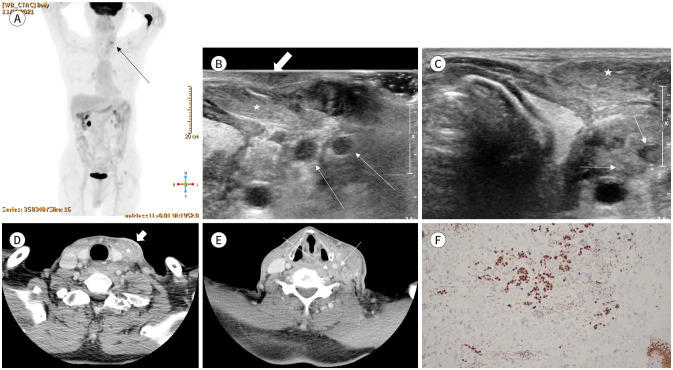

Lymph node metastasis from bladder cancer mainly involves the external/internal iliac and obturator nodes as the primary lymphatic drainage sites of the bladder, and common iliac sites as the secondary drainage. Lymph node involvement above the diaphragm is rare. Metastasis to the head and neck region is associated with poor prognosis and low survival rate. Herein, we report a case of cervical cutaneous and lymph node metastases in a patient with bladder cancer. This is a rare case of advanced urothelial carcinoma presenting as an aggressive inflammatory process with extensive lymph node involvement, without bony or visceral metastasis.